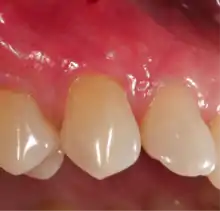

Exposure of the tooth root due to loss of keratinized tissue around the neck of a tooth is referred to as gingival recession. This can result in sensitivity or pain from the exposed tooth root surface (dentin is more permeable and soft compared to enamel and dentin is what makes up the tooth root).[7] Recession may also cause an unasthetic appearance especially if located in the anterior dentition (front teeth). While not all cases of gingival recession require surgical correction, there are various options if that is what the patient desires.[8] It should be reinforced that recession left untreated will not result in tooth loss, contrary to popular belief. Also, recession that is left untreated can be maintained and the inflammation kept at bay with proper brushing and oral hygiene technique.[5] On the other hand, if one desires to pursue corrective therapy, there are a wide variety of techniques ranging from autograft (your own tissue, usually taken from the palate), allograft (someone else's tissue, cadaver), xenograft (animal, usually porcine or bovine) or simply repositioning of the tissue native to the site.[9] The benefits of corrective therapy often result in decreased sensitivity through coverage of the root surface in addition to a gain in the keratinized tissue mentioned beforehand.

A free gingival graft is a dental procedure where a small layer of tissue is removed from the palate of the patient's mouth and then relocated to the site of gum recession. It is sutured (stitched) into place and will serve to protect the exposed root as living tissue. The donor site will heal over a period of time without damage. This procedure is often used to increase the thickness of very thin gum tissue.

A subepithelial connective tissue graft takes tissue from under healthy gum tissue in the palate, which may be placed at the area of gum recession. This procedure has the advantage of excellent predictability of root coverage,[20] as well as decreased pain at the palatal donor site compared to the free gingival graft. The subepithelial connective tissue graft is a very common procedure for covering exposed roots.